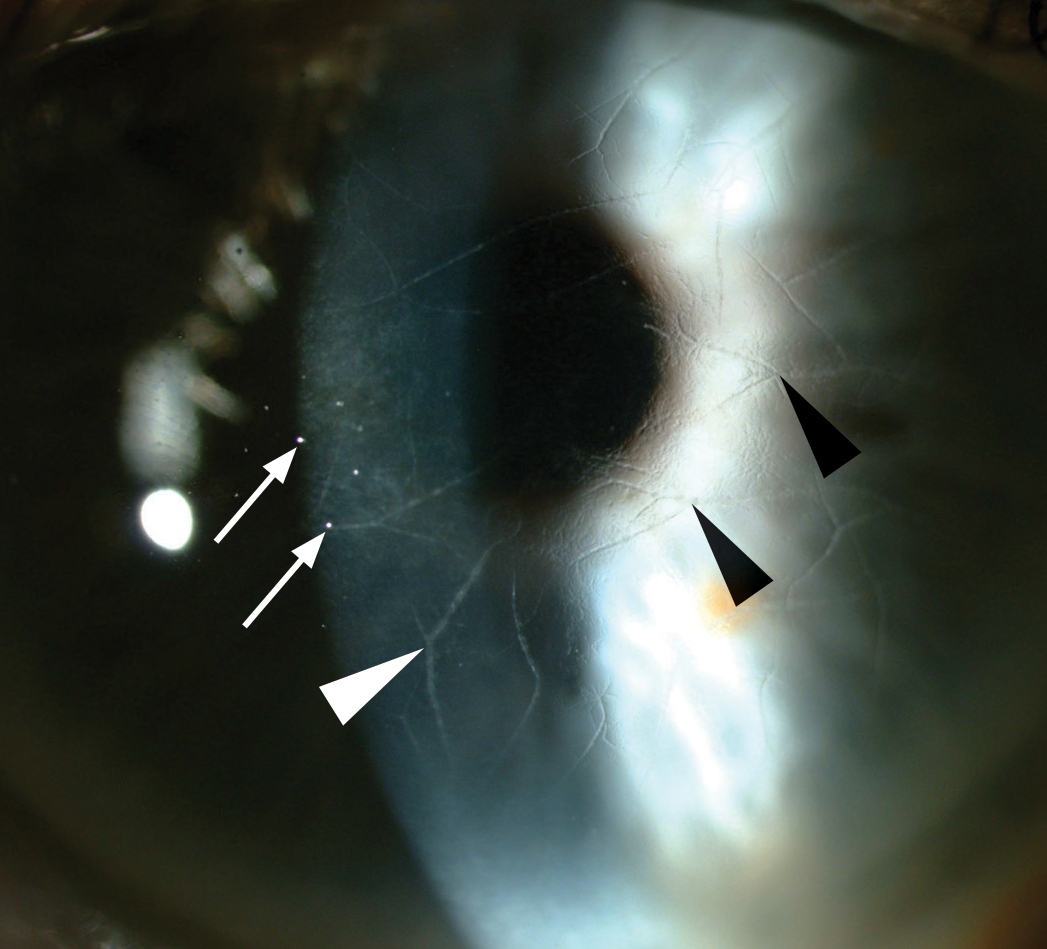

LCD1 presents with branching lattice figures in the stroma with subepithelial opacities and an anterior stromal haze. This condition presents with considerable corneal variation, especially among the variant subtypes. This can make differentiation difficult, particularly with GCD2, which can also present with lattice lesions. Systemic disease can also occasionally present this way, such as in amyloidosis5. (Fig 3)

Fig 3. Refractile, branching lines (arrowheads) in the anterior corneal stroma with subepithelial ovoid white dots (arrows) and anterior stromal haze.